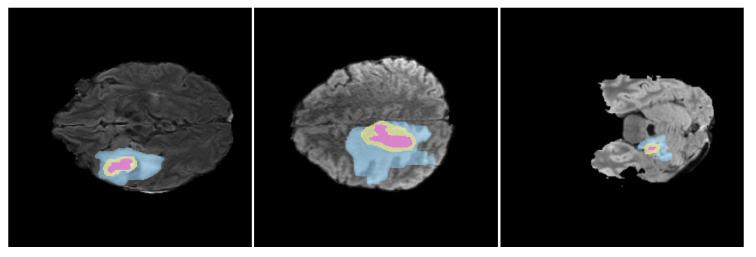

胶质瘤分割的深度学习方法、局限性及未来展望综述

A Review on Deep Learning Methods for Glioma Segmentation, Limitations, and Future Perspectives.

Accurate and automated segmentation of gliomas from Magnetic Resonance Imaging (MRI) is crucial for effective diagnosis, treatment planning, and patient monitoring. However, the aggressive nature and morphological complexity of these tumors pose significant challenges that call for advanced segmentation techniques. This review provides a comprehensive analysis of Deep Learning (DL) methods for glioma segmentation, with a specific focus on bridging the gap between research performance and practical clinical deployment. We evaluate over 80 state-of-the-art models published up to 2025, categorizing them into CNN-based, Pure Transformer, and Hybrid CNN-Transformer architectures. The primary objective of this paper is to critically assess these models not only on their segmentation accuracy but also on their computational efficiency and suitability for real-world medical environments by incorporating hardware resource considerations. We present a comparison of model performance on the BraTS datasets benchmark and introduce a suitability analysis for top-performing models based on their robustness, efficiency, and completeness of tumor region delineation. By identifying current trends, limitations, and key trade-offs, this review offers future research directions aimed at optimizing the balance between technical performance and clinical usability to improve diagnostic outcomes for glioma patients.

摘要